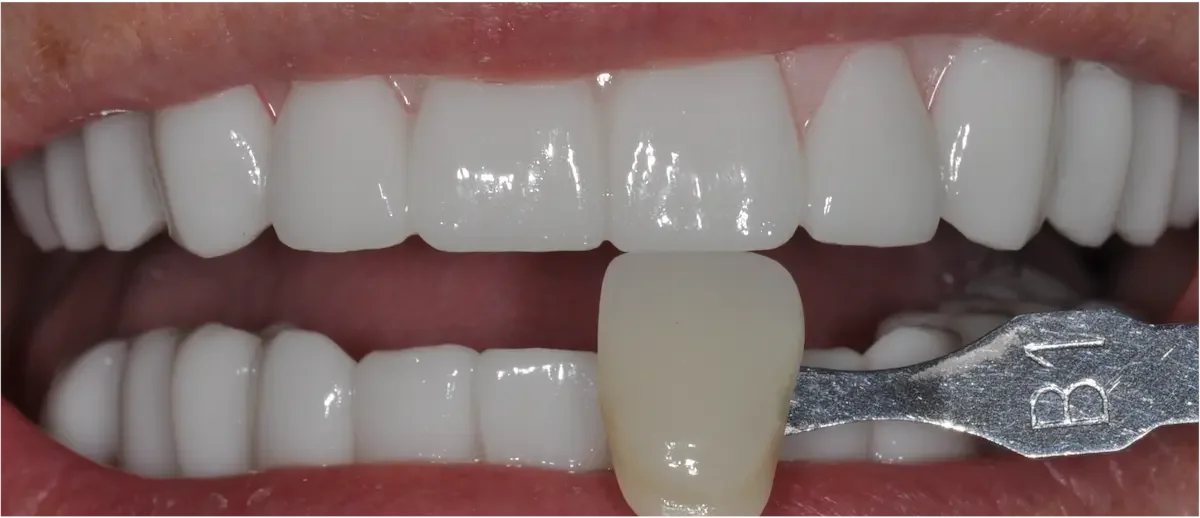

Unlike molars, where strength matters to a higher degree, replacing a front tooth is has much to do with aesthetics, symmetry, and subtlety, in addition to bite force management.

Any tiny mismatch is obvious. The color, shape, gumline — everything has to match the neighboring teeth.

We’re working in the “esthetic zone.” This area demands precise planning, sculpting, and soft tissue support. Thankfully all our doctors have advanced training in cosmetic dentistry.

Once everything is stable, we place the final custom crown. Shade, translucency, shape, and surface texture are all matched to your natural teeth so the implant blends in seamlessly.